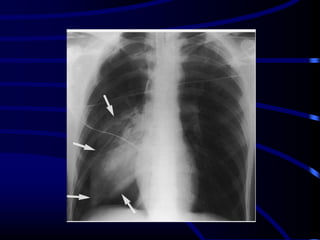

Fallen Lung Sign

This sign refers to the appearance

of the collapsed lung occurring

with a fractured bronchus .

The bronchial fracture results in

the lung to fall away from the

hilum, either inferiorly and laterally

in an upright patient or posteriorly,

as seen on CT in a supine patient.

DD:

Pneumothorax causes a lung to

collapse inward toward the hilum.